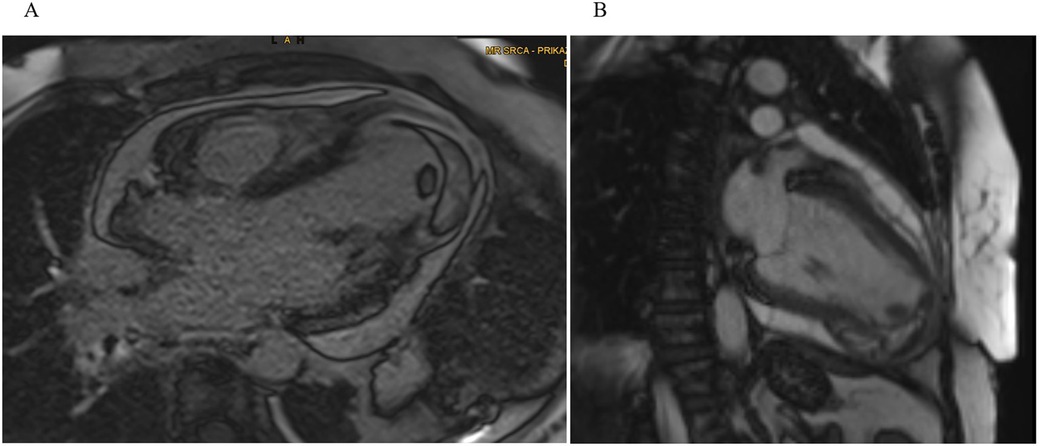

Clinical deterioration and surgical decision

By day 30, the patient again became febrile with rise in inflammatory markers (CRP spiking to 339 mg/L, procalcitonin up to 0.71 µg/L). This prompted a heightened concern for infective hematoma or pericarditis. TTE revealed newly present pericardial effusion along the lateral and inferior wall of the LV with a fluid layer of up to 22 mm. The intramural fluid collection also looked more heterogeneous and potentially communicated with the pericardial space (Figure 3).

Figure 3

Transthoracic echocardiography and computed tomography. (A) Apical four-chamber view showing extensive IDH with marked apical dyskinesia. (B) Apical thrombus formation visualized as an echogenic mass at the ventricular apex. (C) The parasternal long-axis view reveals a moderate, new pericardial effusion along the inferolateral wall of the LV. (D) Axial CT demonstrates a multiloculated, heterogeneous fluid collection within the inferoapical myocardium, with clear communication to a large pericardial effusion along the lateral and posterior walls of the LV. (E) A separate axial CT slice shows a clearly defined, round, intramyocardial lesion.

Because of a suspected rupture or an expanding dissecting hematoma, an ad hoc consultation with cardiovascular surgeons, transplant cardiologists and the CCU cardiology team took place. The plan was to obtain additional imaging to assess the possible communication of the hematoma, evaluate for emergent surgical intervention and complete a “transplant workup” in case the ventricle was too compromised and mechanical support or transplantation were needed post-surgery.

Later that day, the patient underwent additional imaging, including a CT scan of the chest, which showed a large, multi-chambered fluid collection in the inferoapical myocardium, measuring about 65 × 55 × 33 mm, communicating widely through a 20 mm channel with a separate large fluid pocket of approximately 55 × 25 × 100 mm running from the apex along the lateral wall up to the cardiac base (Figure 3). The concern was that the previously noted intramural hematoma had partially liquefied and extended into the pericardial space. The possibility of infection or an abscess could not be fully excluded.